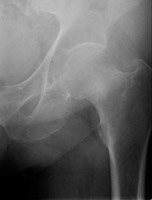

- Click on the image for a larger versionBAP radiograph of the left hip. There is a subtle band of sclerosis at the femoral neck.